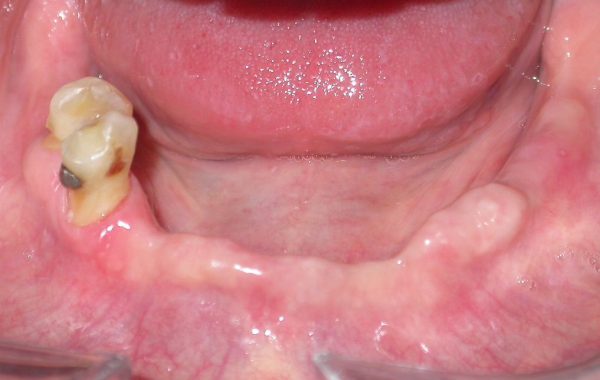

En este caso tenemos una paciente de 47 años de edad, la cual padecía periodontitis severa. Se le realizó el tratamiento periodontal, los dientes inferiores se conservaron pero en la parte superior la mayoría de los dientes se tuvieron que extraer debido a la gravedad de la enfermedad y la gran movilidad que los dientes presentaban.

caso 3-1

Debido a la enfermedad periodontal la paciente perdió mucho hueso, por lo cual se en la parte superior se realizaron elevaciones de senos maxilares (ver injertos óseos), para poder colocar implantes dentales y así sustituir los dientes perdidos.